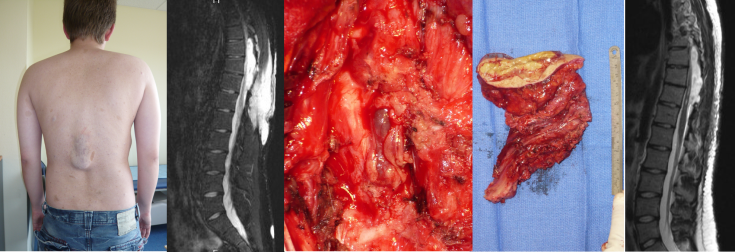

les méningocèles iatrogènes

ici méningocèle après chirurgie pour myélolipome ; la cavité opératoire est rapidement colonisée par des cellules méningothéliales qui lui donnent un aspect structuré ; pourtant, la paroi n’a pas de consistance véritable et ne peut pas être utilisée pour une plastie ; il est nécessaire de réaliser une fermeture durale avec éventuellement un patch prothétique, et de protéger la suture par un drain lombaire externe mis en place au cours de l’intervention au dessus de l’ouverture durale.